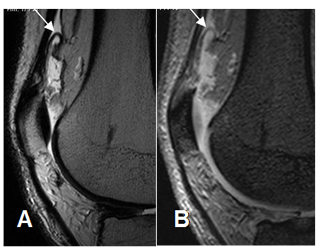

Fig 157. Plica suprapatelar.

A: RM sagital en FFE y B: RM sagital en T2. Derrame articular y signos de sinovitis.

Imagen serpentiginosa a nivel suprapatelar, que corresponde a plica.